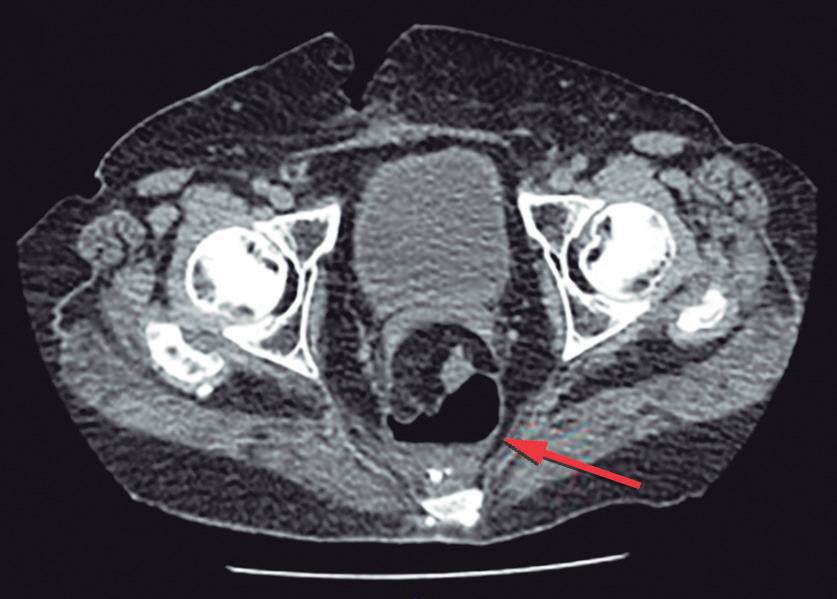

El absceso anal se presenta como un cuadro anal doloroso de desarrollo progresivo, y la intensidad del dolor se acrecienta en el transcurso de unos pocos días.11 (Figura 11)

Figura 11. Absceso anal posterior con abultamiento fluctuante de la piel tenso y doloroso

El mismo puede asociarse a algunos síntomas sistémicos como fiebre, malestar general y leucocitosis. En el examen físico se presenta como un tumor con eritema cutáneo, con aumento de la temperatura. Presenta tensión, puede fluctuar y produce intenso dolor durante la palpación. En el caso de los abscesos interesfintéricos el dolor puede ser muy intenso, pero no evidenciarse el absceso durante la inspección anal o palpación. Habitualmente, el dolor hace imposible la realización del tacto rectal.11 En los casos de sospecha diagnóstica o de requerir un estudio topográfico del absceso la realización de una tomografía con contraste o una resonancia ayuda en el diagnóstico y puede guiar la elección de la vía de drenaje.19 El tratamiento del absceso es quirúrgico con la realización de un drenaje transcuatáneo o transrectal.20 Es conveniente aclarar al paciente que es posible que durante la cicatrización se desarrolle una fístula anal. Esto ocurre en más de la mitad de los pacientes, más frecuentemente en las mujeres con fístulas anteriores.21